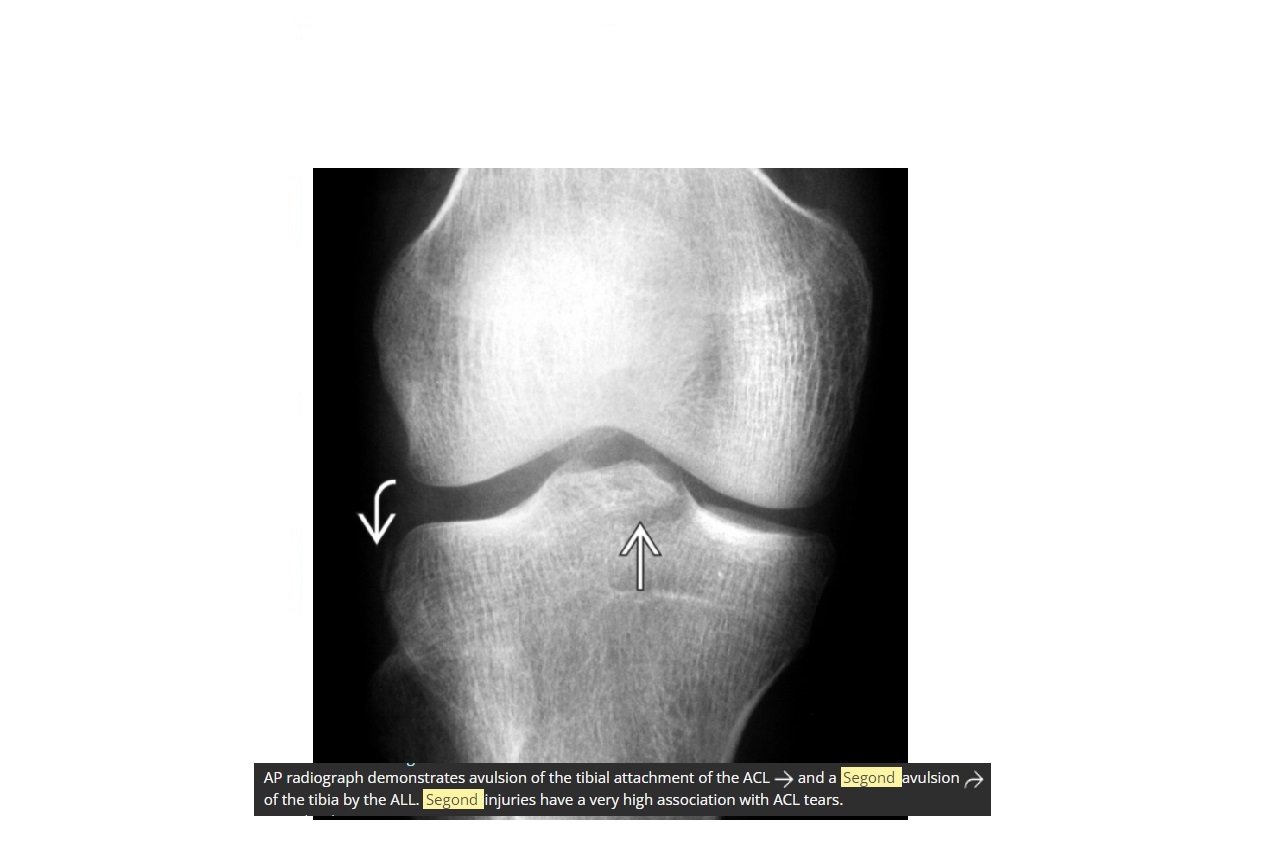

Segond fracture

Lateral tibial plateau

Associated with ACL tear (75%) and internal rotation

MR SL = Medial Reverse Lateral Segond

How well did you know this?